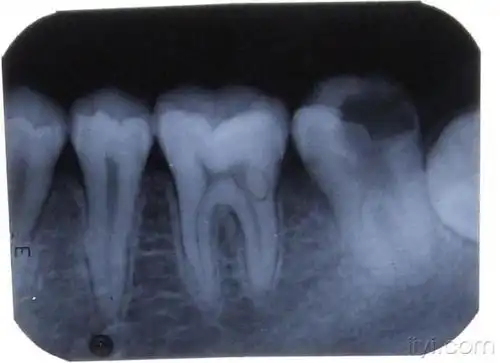

〈附牙片〉 - 口腔医学专业讨论版 - 爱爱医医学论坛 - 爱爱医医学网